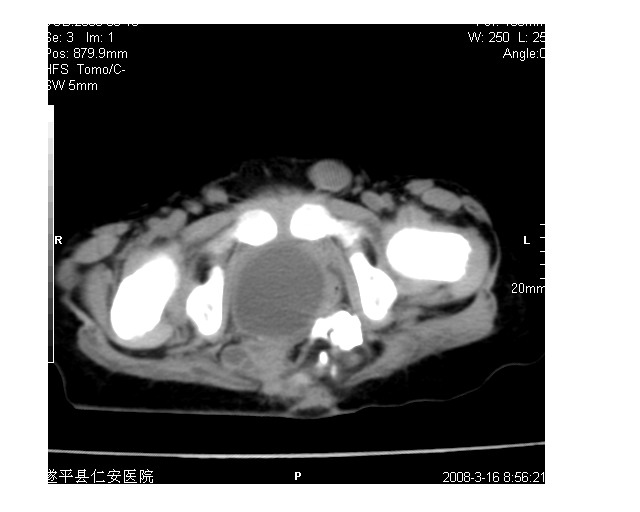

以下是引用lkc8963在2008-3-16 12:49:00的发言:[br]盆底巨大混杂密度肿块,富含多种组织成分包括脂肪/液体/软组织/钙化,边界清楚,向前压迫肠管及膀胱,向后突入骶尾部皮下脂肪层,首先考虑畸胎瘤,诊断时需要与脊柱裂/囊性淋巴管瘤等区别。